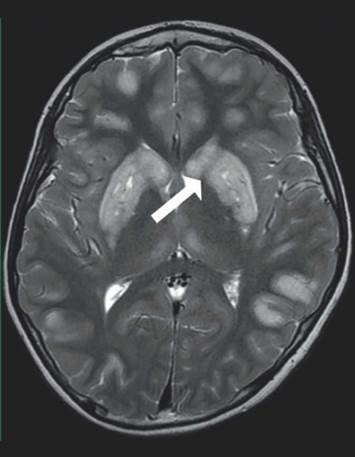

Los casos presentados cumplen los criterios de diagnóstico definidos por Rahman en 1996; que establecen al SL como una enfermedad neurodegenerativa con compromiso motor y cognitivo, con signos o síntomas de compromiso en tallo cerebral o ganglios basales, asociado a niveles elevados de lactato en plasma o LCR (los valores pueden ser normales en el 25 % de los casos) y presencia de lesiones características en neuroimágenes por RMC o estudios anatomopatológicos 5,11,12. Los hallazgos en RMC se caracterizan por presencia de lesiones hi-perintensas en T2 simétricas, bilaterales principalmente en ganglios basales o tallo cerebral más específicamente en sustancia nigra, núcleo rojo y en médula o presencia de lesiones hipodensas en ganglios basales en la TAC 1,6,14. No obstante, las lesiones se pueden presentar en otras áreas típicas, como cordón espinal, tálamo y cerebelo 5,13. A nivel de RMC es posible identificar lesiones en sustancia blanca, que son confluentes, simétricas y bilaterales, y en ocasiones pueden ser confundidas con una leucodistrofia; estos pacientes pueden presentar lesiones tipo accidente cerebro vascular, atrofia cortical o cerebelosa y compromiso simétrico en núcleos olivares y dentado 14. Estudios complementarios con MRS cerebral, como los realizados en los pacientes presentados, permiten demostrar elevación de los picos de lactato tanto en tejido aparentemente normal como en parénquima afectado 4,15,16.

Todos los pacientes de este reporte presentaron compromiso imagenológico en ganglios basales y en uno de ellos se preservaron las estructuras en tallo cerebral (figura 1). El compromiso de sustancia blanca difusa de predominio frontal se presentó en uno de los pacientes en el que además se observó presencia del pico de lactato por espectroscopía en esta región y en los ganglios basales.